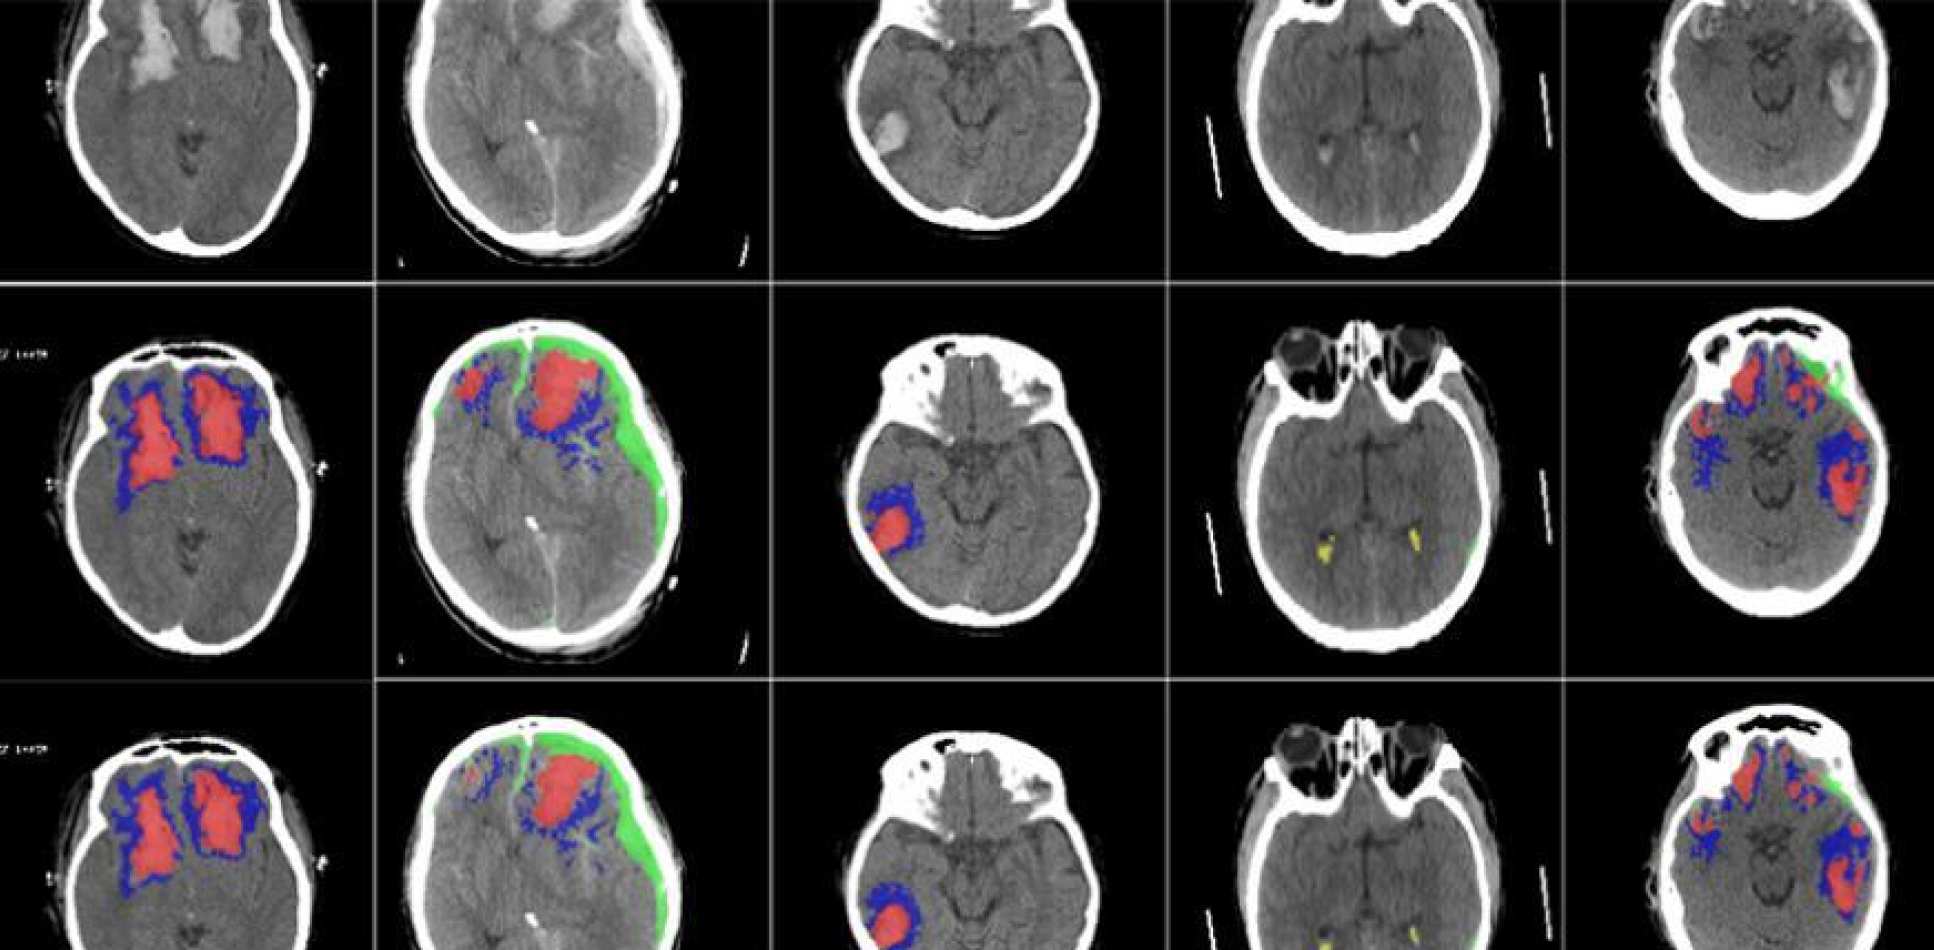

Image of brain scans processed by the machine learning algorithm

Researchers at Imperial College London and Cambridge have developed an AI algorithm that can detect and identify different types of brain injuries.

The researchers found that their machine learning algorithm was able to detect, segment, quantify and differentiate between types of brain lesions using images of CT scans.

Detailed assessment of a CT scan with annotations can take hours, especially in patients with more severe injuries, so the researchers designed an AI-based tool to automatically identify and quantify the different types of brain lesions from CT scans.

Imperial researchers developed a machine learning tool based on an artificial neural network, developed by Imperial's Miguel Monteiro and Dr Ben Glocker. They trained the tool on more than 600 different CT scans showing brain lesions of different sizes and types, before validating the tool on an existing large dataset of CT scans.

The AI was able to classify individual parts of each image and tell whether it was normal or not. The researchers say this could be useful for future studies in how head injuries progress, since the AI may be more consistent than a human at detecting subtle changes over time.